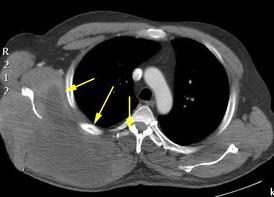

Densidad similar al músculo con estriaciones internas de grasa

Hallazgo incidental . Región infraescapular 2% de TC del tórax. Bilateral 60%.

Burt AM et al. Imaging review of lipomatous musculoskeletal lesions. SICOT J2017/ Murphey MD et al. From the archives of the AFIP: benign musculoskeletal lipomatous lesions. Radiographics. 2004